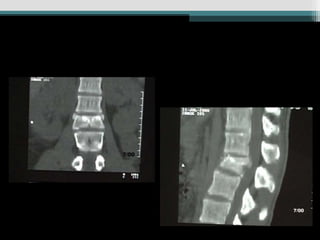

• TC - Visualiza melhor colunas média e posterior ;

fraturas obscuras ; estreitamento canal e

fragmentos ; orienta tratamento cirúrgico ;

útil quando o déficit não corresponder a lesão

(incompleto).